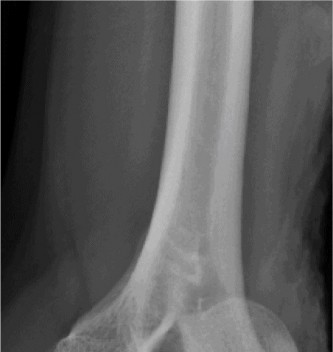

It should be noted that reverse total shoulder arthroplasty is also the procedure of choice in patients with cuff-tear arthropathy (aka rotator cuff arthropathy). Characteristics of cuff-tear arthropathy include superior migration of the humerus due to a massive rotator cuff tear, glenohumeral joint destruction, subchondral osteoporosis, and humeral head collapse (see Fig. 2–17). A reverse total shoulder

Figure 2–17_X-rays of a patient showing evidence of cuff tear arthropathy. The humerus is migrated superiorly, the glenohumeral joint is destroyed, there is subchondral osteoporosis, and the humeral head is collapsed. (From Ecklund KJ, Lee TQ, Tibone J, Gupta R. Rotator cuff tear arthropathy. _J Am Acad Orthop Surg. 2007;15(6):340–349.)